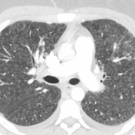

Radiology Quiz

07/07/2021

A 15-year-old boy presented to the emergency department with acute onset of right knee pain. While playing basketball, the patient had attempted a layup and had felt a “popping” sensation in midair. He was...